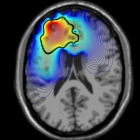

Biomathematics

The group applies state-of-the-art mathematical and computational techniques to address research problems from biosciences, life sciences, and medicine. Our aim is to develop predictive mathematical and statistical models and computational approaches to tackle topical biologically-relevant questions.

We develop and analyse novel computational and numerical methods, studying their applications to multiple areas such as Computational Topology, Data Science, Lattice Gauge Theory, Mathematical Biology, Cancer Research and Applied Algebraic Geometry.